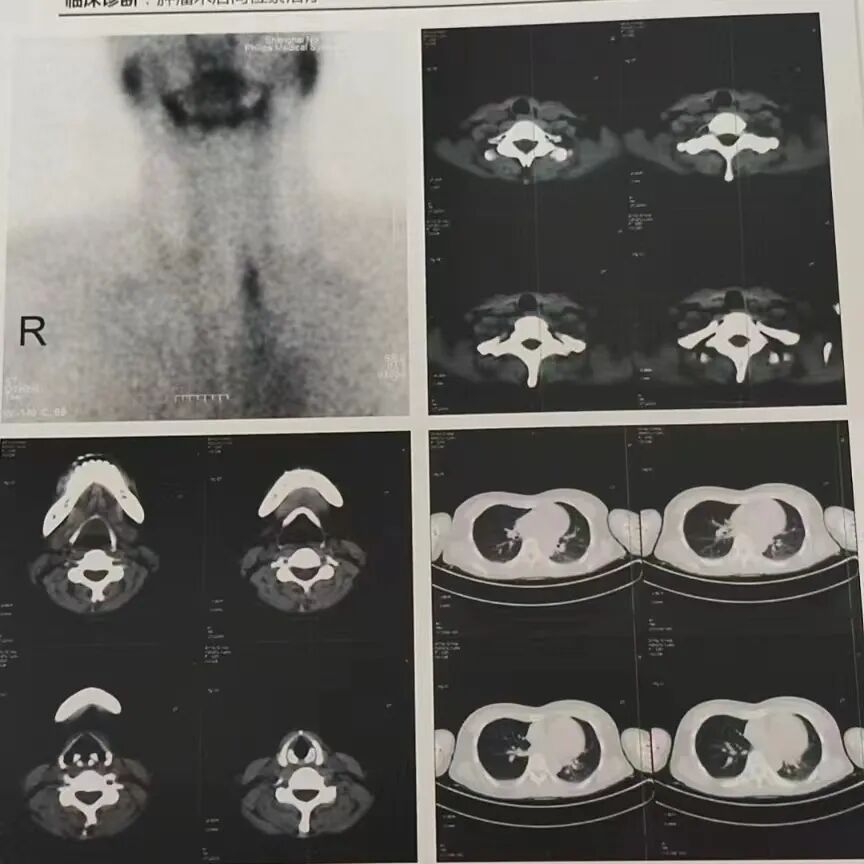

2021-05-10    PETCT

病史及检查目的:

患者因“发现甲状腺结节”于2017-01-06在我院行“甲状腺癌根治术+左叶全切+右叶近全切+中央区淋巴结清扫+喉返神经探查术”,病理结果:(左叶)甲状腺乳头状癌,(右叶)滤泡性肿瘤;左侧中央淋巴结、右侧中央淋巴结转移性甲状腺乳头状癌。2017-11-30再次手术,于我院神经外科行“1、颅骨病灶切除术;2、脑膜病灶切除术;3、颅骨钛板修补术:4、脑膜修补术”,术后患者一直服用“优甲乐“治疗;共行4次同位素治疗,未次治疗时间:2019-04-10.2019-04-08于我院行PET/CT.此次入院拟行核素治疗。

诊断意见:

1、“甲状腺Ca根治术”后,双侧颈部IV区、左侧锁骨区多个淋巴结影,FDG代谢不高;右肺上叶段和右肺下叶前、外基底段结节影,FDG代谢不高;右侧肩胛骨、T11椎体、右侧髂骨及左侧股骨段多发骨质破坏,右侧第5肋局部密度增高,部分病灶FDG轻度代谢增高,符合多发骨转移瘤表现以上与2019-4-10PET/CT老片比较均相仿。

2、右侧上颌窦慢性炎症;双侧鼻咽部和扁桃体炎症:双侧颈部1、II区慢性炎性淋巴结。

3、与2019-4-10PET/CT老片,左肺上叶尖后段、下舌段磨玻璃结节,较前相仿,建议薄层CT随左肺下叶后基底段慢性炎症;胸腺退化不全;少量心包积液;双侧少量胸腔积液、双侧胸膜稍增厚左侧斜裂胸膜钙化灶。

4、左乳内下象限和右乳外上象限局灶性FDG高代谢灶,建议MRI检查。

5、肝右叶囊肿;左肾血管平滑肌脂肪瘤。

6、子宫腔内片状代谢增高;双侧附件区囊实性密度影伴代谢不均匀增高;盆腔少量积液;以上考虑生理周期有关,请结合临床。

7、L4椎体、双侧髋臼及股骨头骨岛;脑FDG代谢未见明显异常;右侧颅骨术后改变。